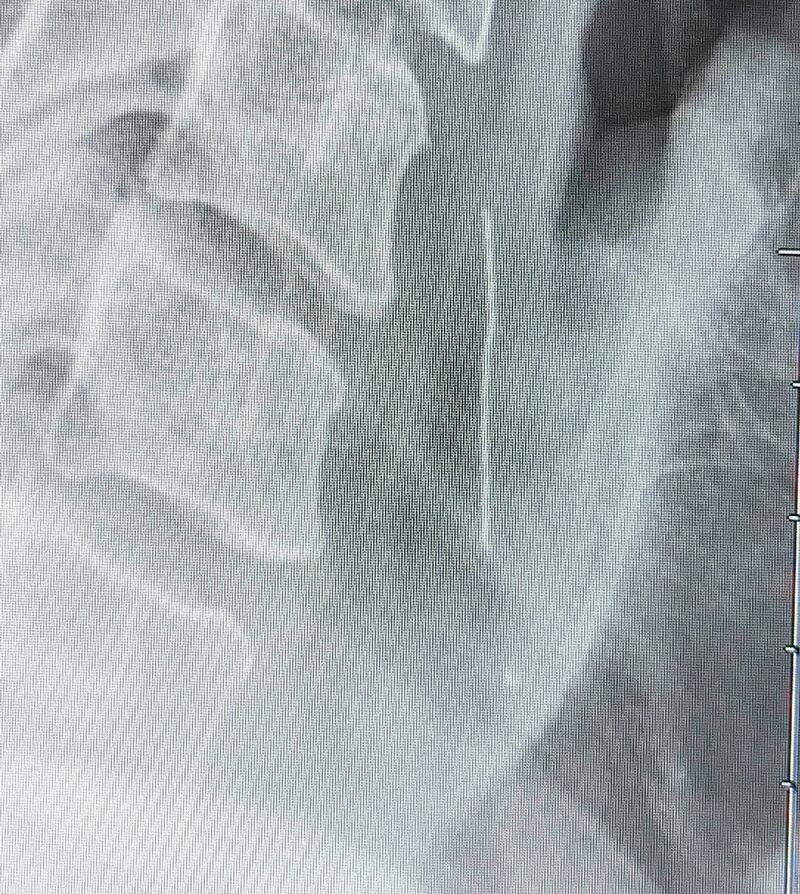

The culprit was clearly visible on X-ray: A thin piece of wire was lodged in his throat. It was a bristle from a metal brush used to clean the barbecue grill.

As for Richards, it was in a third surgery using live X-rays as they went that the bristle was successfully removed. The surgeon told him he’d had a similar case where the patient’s esophagus was quite damaged.